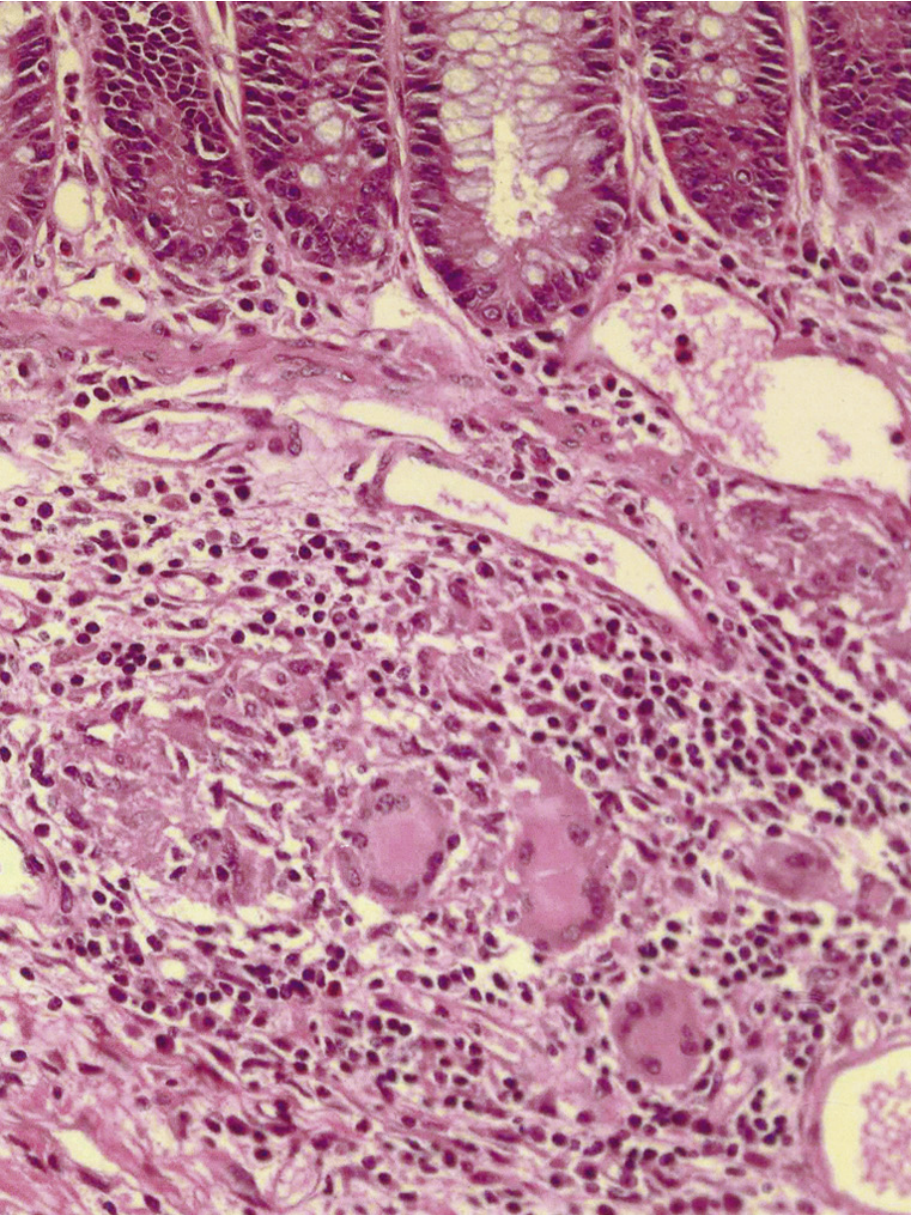

• Granulomas — Sarcoid-like, non-caseating collections of epithelioid histiocytes, lymphocytes, and eosinophils. Highly characteristic of CD (though not universal — found in 9–66% of cases depending on sampling). Unlike tuberculosis, there is no central necrosis and acid-fast stains are negative. Granulomas may be found in any layer of the intestine, mesenteric lymph nodes, and even extraintestinal sites (skin, eye, liver).

Photomicrograph of a typical CD granuloma — loosely formed collection of multinucleated giant cells and epithelioid macrophages, no central caseation

Photomicrograph of a typical CD granuloma in an endoscopic biopsy: loosely formed collection of multinucleated giant cells and epithelioid macrophages. No central caseation. (Sleisenger and Fordtran's GI and Liver Disease)